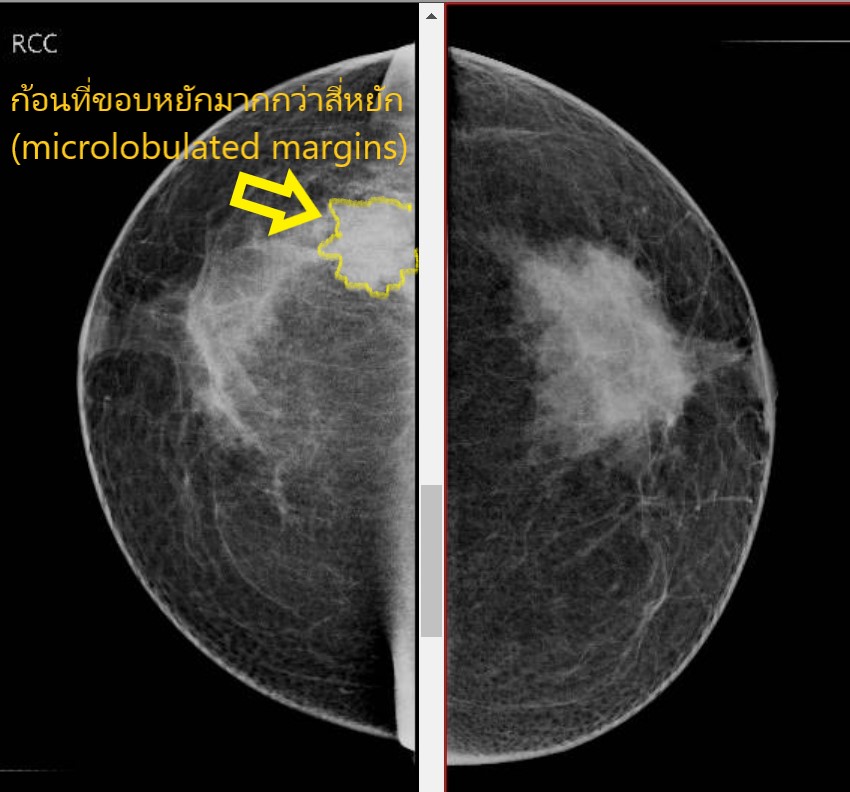

DrRattawachIR: ก้อนในเต้านมบนภาพแมมโมแกรม